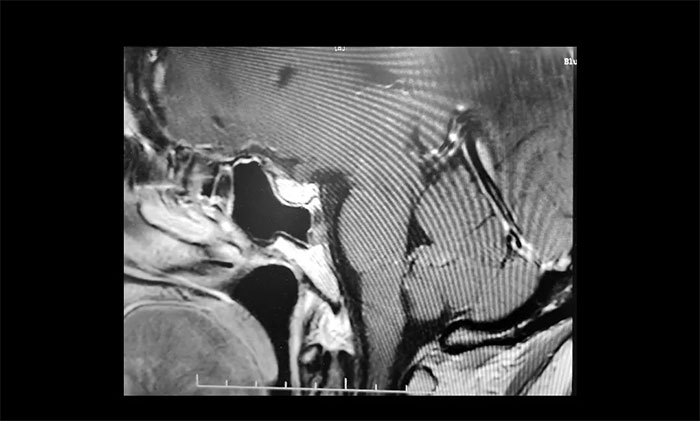

▲ 术后影像显示肿瘤被切除